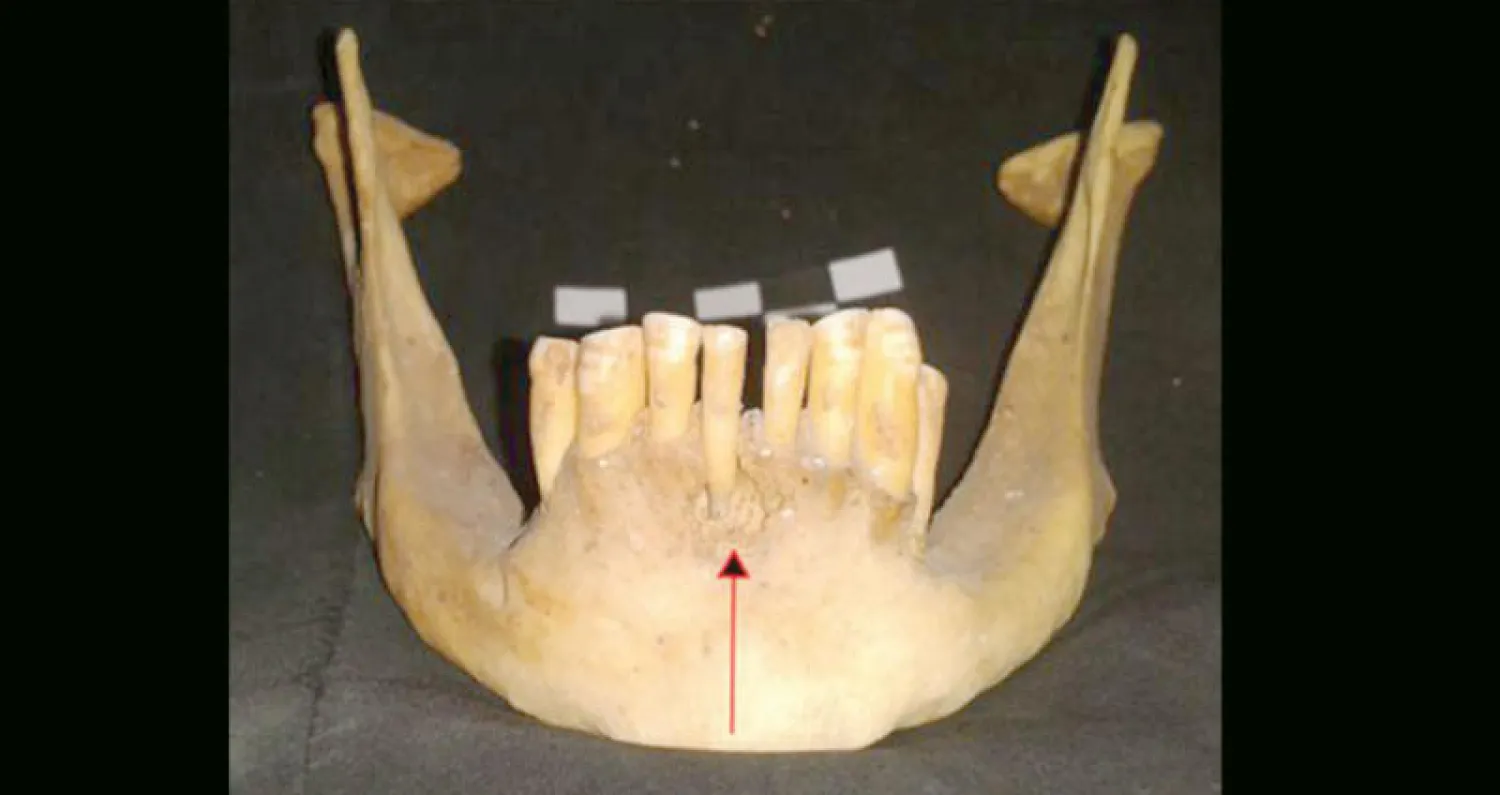

عينات أسنان الفك التي تعود لمومياوات فراعنة صحراء مصر الغربية